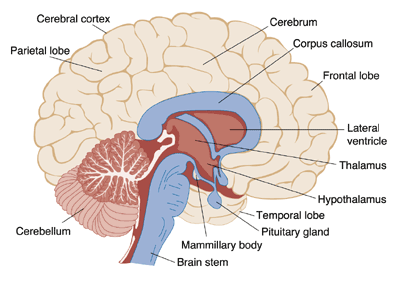

Many researchers believe that the entire brain is involved with memory, in some way or another (Lashley, 1950). However, some key areas have been identified (shown below in Figure 1.) and include the amygdala, hippocampus, cerebellum, the prefrontal cortex and the synapses linking them all (Mayford, Siegelbaum, & Kandel, 2012).

However, as research has developed, and the mapping of the brain and its functions has developed researchers are becoming able to pinpoint the structure’s role within memory, such as the amygdala facilitating the encoding of memories to a more significant degree when the event is emotionally arousing (Josselyn, 2010). This means that when an individual suddenly fails to respond to stimuli that normally would have induced a fear response; a neurologist can narrow down their investigation and begin imaging of the amygdala with the expectation of some sort of abnormality (e.g. a lesion or tumour) affecting it’s functioning.